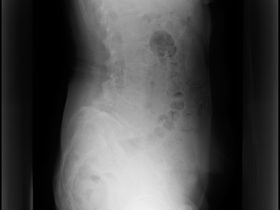

腰椎すべり症を伴う脊柱管狭窄症の原因と症状及び治療方法

「腰椎すべり症を伴う脊柱管狭窄症の原因と症状及び治療方法」 私たちの体は、年をとるにつれ、時間とともに変性することがあります。 その中の一部では、遺伝的要素のために特定の変性状態になることもあります。 …